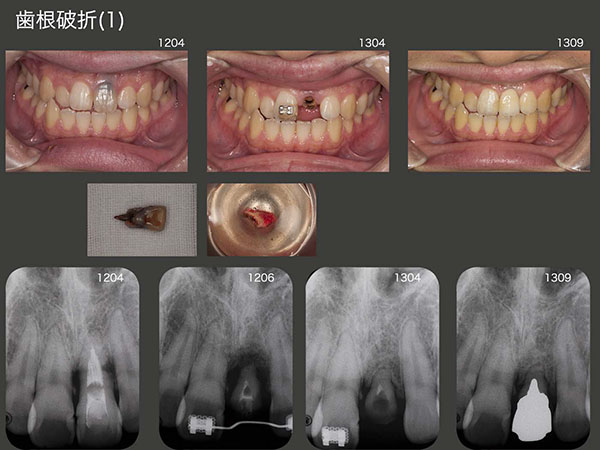

3.歯根破折(1)

2012年4月初診,23歳の男性.左上1は10歳の時に転倒して,折れた歯を戻した.その後およそ2年ごとに腫れを繰り返してきたが,最近歯の動揺が大きくなったので来院したとのこと.デンタルX線写真から炎症性の歯根吸収らしき像がみられた.通常であれば抜歯し,両側の健全歯を削ってブリッジを装着する症例であるが,何とか左上1を保存したいと考えた.

まず,左上1の矯正的挺出を試みたが,歯根破折が生じていたため,破折部位より上部のみが挺出されてしまった.そこで矯正的挺出を諦め,12年5月に残根の抜歯を試みた.何とか愛護的に抜去することができたので,歯肉縁上歯質が得られるところまで挺出させた位置に再植,固定した.約1年間暫間被覆冠で経過観察を行い,特に問題がなかったので,13年9月に硬質レジン前装冠を装着した.歯根が短いために動揺が生じ,固い食品を前歯で嚙み切れないのが欠点であるが,患者さんは特に不満を訴えていない.

臼歯部ならば連結固定は必須であるが,前歯は機能させなければ単独植立も可能である.